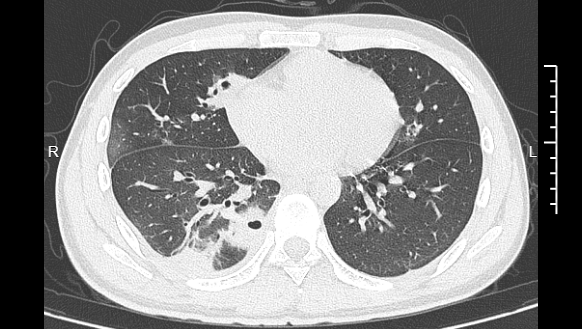

熬到第三天,小林已经烧到39℃,赶紧去医院就诊。接诊的医生一看他的症状,立刻安排了CT检查。结果显示:小林的肺里有十几个空洞,部分肺组织已经坏死,这是典型的血源性肺脓肿。

▲小林的CT影像显示肺里有多个空洞